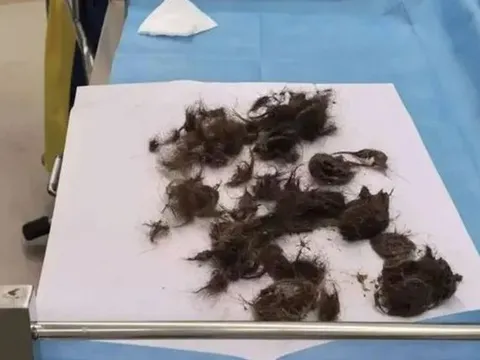

Từ mẫu thực vật do người nhà bệnh nhân mang đến, các bác sĩ xác định đây là cây cần dại - một loài thực vật cực độc. Loài cây này dễ bị nhầm lẫn với một số cây ăn được như cà rốt dại, mùi tây, cần tây dại hoặc các loại rau mọc hoang, khiến người dân vô tình thu hái về làm thực phẩm.

Cây cần dại 3 người ăn phải nhập viện gấp. Ảnh: Bệnh viện cung cấp.

Qua thăm khám và khai thác tiền sử bệnh bác sĩ Đô xác định thủ phạm gây ngộ độc là cây cần nước độc (tên khoa học Conium maculatum). Loài thực vật thuộc họ hoa tán này chứa hợp chất alkaloid cực độc trong toàn bộ rễ, thân, lá, hoa và hạt. Độc chất tác động trực tiếp lên hệ thần kinh cơ, cắt đứt quá trình dẫn truyền xung động, gây liệt tiến triển. Nạn nhân ăn phải sẽ đổ mồ hôi nhiều, giãn đồng tử, tăng tiết nước bọt, tim đập nhanh, lú lẫn và có thể tử vong do suy hô hấp cấp hoặc ngừng tim nếu không cấp cứu kịp thời.